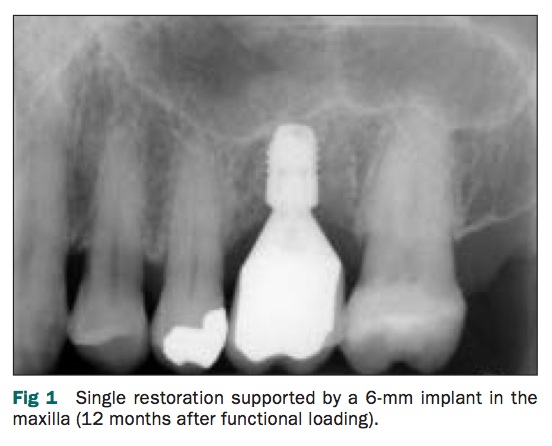

我們知道有短植體的存在, 目前的文獻來說少於10mm就是短植體了, 而有文獻是說若是crown/root ratio大於3.4是不好的. 這個回顧性的研究是在37位患者的上或下顎種植6mm的Astra Osseospeed 4.0, 共有47支. 平均的C/R ratio為2.14+-0.42. 然後至少追蹤一年.

結果marginal bone loss平均0.13mm,也沒有任何failure, 但是數量和追蹤時間都太少, 需要更多的研究來佐證.